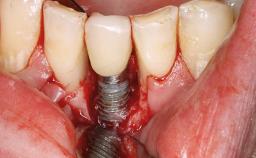

Peripheral Giant-cell Granuloma Associated with Peri-implant Tissues

Giant-cell granulomas (GCG) of the jaws are benign reactive lesions of unknown etiology, unrelated to giant-cell tumors (osteoclastomas), which are defined as benign but locally destructive and aggressive neoplasms (Jundt and coworkers 2005). Depending on their localization at the initial diagnosis, GCG are dived into central (CGCG) and peripheral (PGCG) types. CGCGs occur within the jawbones and appear as unilocular or multilocular radiolucent lesions. The incidence in the general population is very low. They are more commonly found in the mandible, mainly in children and young adults—patients are generally younger than 30 years—and have a greater incidence in females (Heithersay and coworkers 2002). The clinical behavior of CGCGs varies from slowly growing asymptomatic swellings to aggressive lesions that may result in pain, cortical perforation of the affected jaw site, and root resorption (de Lange and coworkers 2007).

SAC Level Advanced

Defining Characteristics More than three missing teeth to be replaced with an implant-borne prosthesis or prostheses